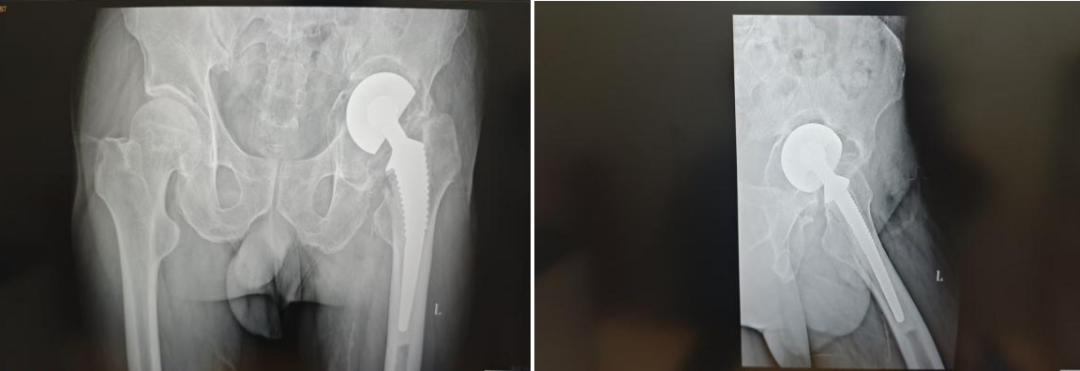

患者为一名髋关节严重受损的男性,其髋臼前柱,上柱及后柱存在大面积骨缺损,传统手术方法因难以重建垂直及水平偏心距而面临极高风险——偏心距偏差可能导致关节撞击、下肢不等长、肌肉无力甚至假体脱位。此外,常规3D打印臼杯因形态适配困难,无法满足患者需求。

术前正位(左)术前侧位(右)

面对这一难题,林源主任医师团队决定采用国际较为领先的“杯中杯”技术。该技术通过精准利用残留宿主骨,压配植入多孔钽金属杯,重建髋臼巨大骨缺损;随后在钽杯基础上安放定制骨水泥臼杯,精准恢复髋关节旋转中心及生物力学偏心距。术中,林源主任医师团队依据术前3D影像建模数据,精确计算钽杯直径与位置,最终实现假体稳定支撑与关节功能重建。